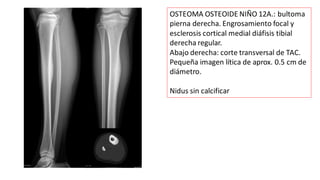

OSTEOMA OSTEOIDE NIÑO 12A.: bultoma

pierna derecha. Engrosamiento focal y

esclerosis cortical medial diáfisis tibial

derecha regular.

Abajo derecha: corte transversal de TAC.

Pequeña imagen lítica de aprox. 0.5 cm de

diámetro.

Nidus sin calcificar